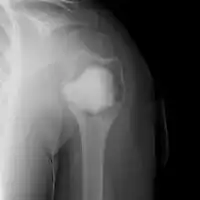

X-ray and CT scan show lytic expansion lesions with clear borders.[1] Expansion of cortex gives the lesion a balloon-like appearance. Larger lesions may appear septated.[10] MRI reveals fluid levels.[1] Bone scan shows outer radiotracer uptake, with a central dark area.[1]

ABC shoulder -